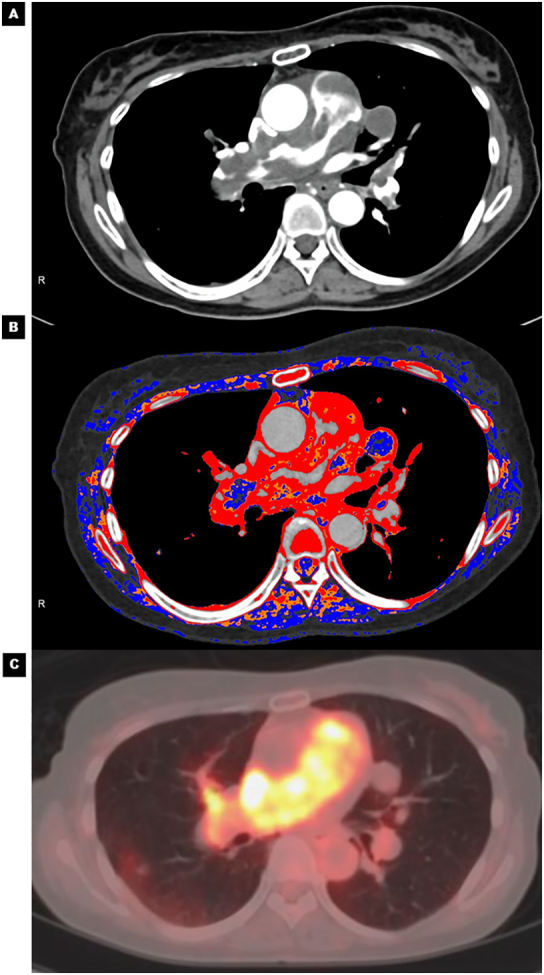

On admission, her blood pressure was 100/60 mmHg and heart rate was 90 bpm with sinus rhythm. D-dimer and brain natriuretic peptide (BNP) levels were slightly elevated (D-dimer = 4.3 μg/ml; reference <1.0 μg/ml and BNP = 62.5 pg/ml; reference ≤18.4 pg/ml). Chest X-ray showed dilated central pulmonary arteries, suggesting pulmonary hypertension (Fig. 1A, yellow arrows). A large mass that moved back and forth across the pulmonary valve was found by echocardiography (Fig. 1B, Online Video 1). A color Doppler ultrasound detected moderate tricuspid regurgitation with a pressure gradient of 88 mmHg, which confirmed the presence of pulmonary hypertension. Contrast-enhanced CT revealed filling defects occupying in the main pulmonary trunk extending to bilateral pulmonary arteries (Fig. 1C, yellow arrows). There was no sign of metastatic tumors originating from other organs. Suspecting a pulmonary artery tumor, 18F-fluorodeoxyglucose (FDG)-PET/CT was performed to rule out PE. Intense FDG-uptake was observed in the pulmonary arteries, particularly at the main pulmonary trunk. This finding strongly suggested pulmonary artery tumor (Fig. 1D, yellow arrow). There was a high maximum standardized uptake (max SUV) of 13.2. The red color-coded region of iodine map (Fig. 2B) using dual-energy CT (Fig. 2A) was a near match for the PET image of the FDG-uptake region (Fig. 2C). The detailed protocol for CT analysis and its validation in other cases are described in the Online materials.

Fig. 2.

Visualization of pulmonary artery intimal sarcoma by color-coded iodine map: comparison between contrast-enhanced CT, iodine map, and PET/CT. (A) Contrast-enhanced CT showing the filling defects showing the disease distribution. (B) Dual-energy CT shows good correspondence between the red color-coded region of the iodine map and (C) the intense FDG-uptake region using PET/CT.

CT, computed tomography; FDG, 18fluoro-2-deoxyglucose; PET, positron emission tomography.